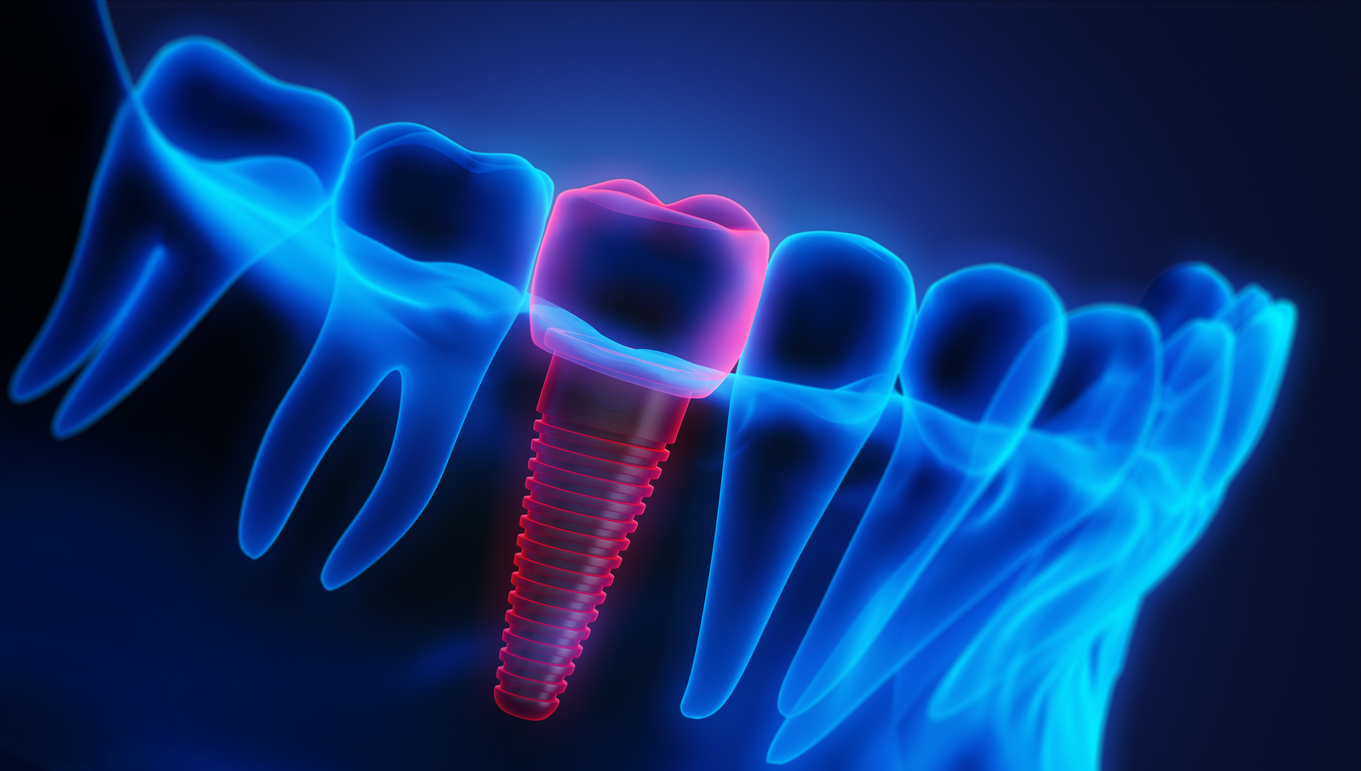

What are dental implants?

A dental implant is a small, biocompatible screw, usually made of titanium, that acts as a replacement for a natural tooth root. Surgically placed into your jawbone, the implant fuses with the bone over time in a process called osseointegration. This creates an incredibly strong and stable foundation for a replacement tooth, crown, or bridge. Unlike dentures, which can slip or cause discomfort, implants offer a permanent solution that looks, feels, and functions just like your natural teeth.

At the heart of modern implantology is Cone Beam Computed Tomography (CBCT). This advanced technology takes detailed 3D X-ray images of your teeth, jawbone, nerves, and surrounding structures. Unlike traditional 2D X-rays, a CBCT scan provides a comprehensive view from every angle, which is essential for accurate treatment planning.

- Precision planning: The 3D images allow your dentist to measure bone depth, thickness, and density with incredible accuracy, ensuring they choose the right size and type of implant for you.